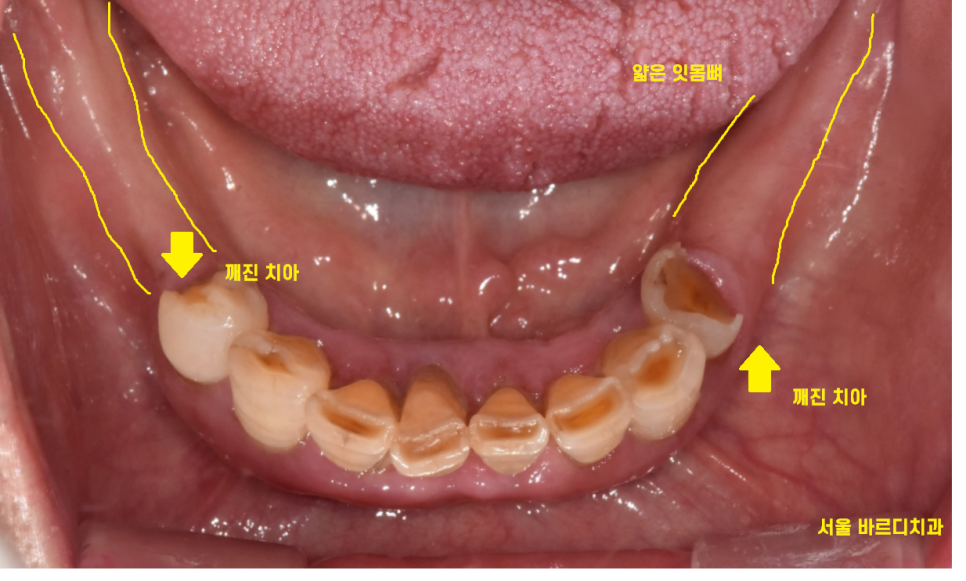

23.08.17

아래 치아의 경우 깨지고

치아가 뽑힌지 오래되어 잇몸뼈가 얼마 없는 상황이었습니다.

23.10.10

발치 후 치아의 모습이죠~?